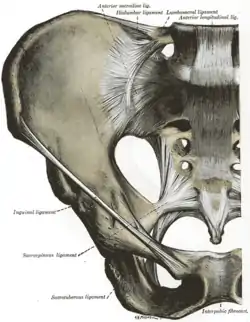

Ligaments

| Ligament | From | To |

| broad ligament of the uterus | uterus | side of pelvis |

| * mesovarium | ovary | |

| * mesosalpinx | Fallopian tube | broad ligament of the uterus |

| * mesometrium | ||

| cardinal ligament | cervix and vagina | pelvic wall |

| ovarian ligament | ovary | uterus |

| round ligament of the uterus | ovary | travels through inguinal canal, ends at mons pubis |

| suspensory ligament of the ovary | ovary | pelvic wall |

Joints of the pelvis. Anterior view.

Joints of the pelvis. Anterior view. The arteries of the pelvis.